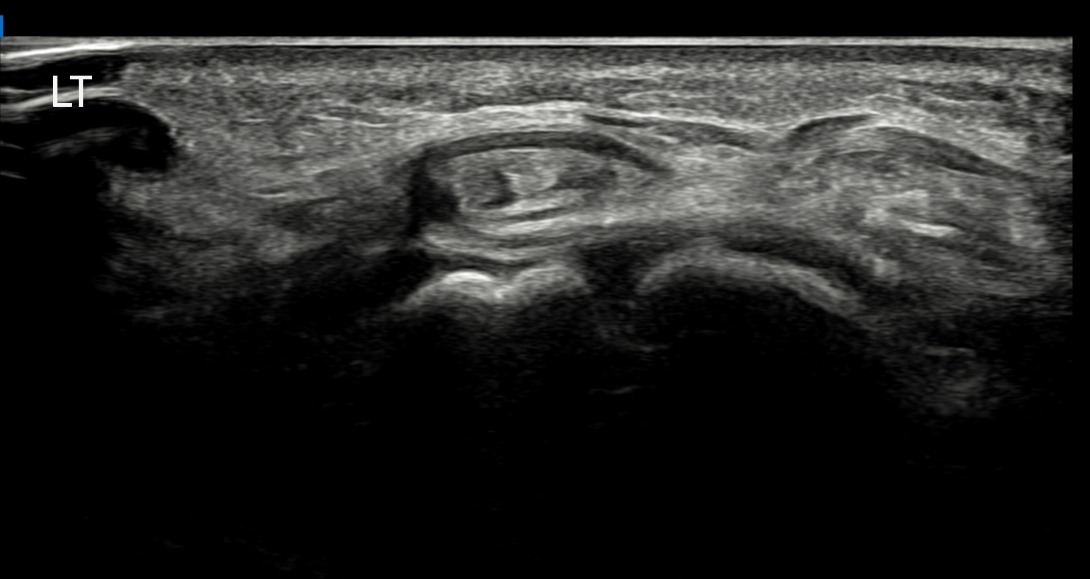

치료 후기에 사용된 전/후 검사 사진은 동일 인물의 결과이며 각 지점 동일 조건에서 촬영되었습니다.

개인에 따라 치료 결과에 차이가 있을 수 있으며, 부작용이 발생할 수 있습니다. 내원 후 충분한 상담을 받으시고 치료를 진행하시면 됩니다.

- 치료기간 : 25 . 4 . 25 ~ 25 . 6 . 25

- 치료횟수 : 1Cycle(5 회)